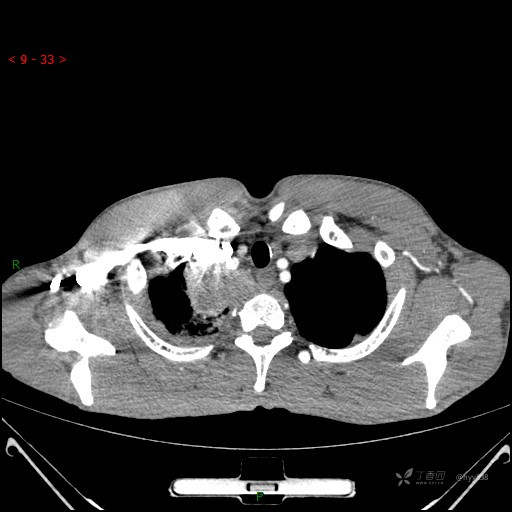

胸部CT平扫